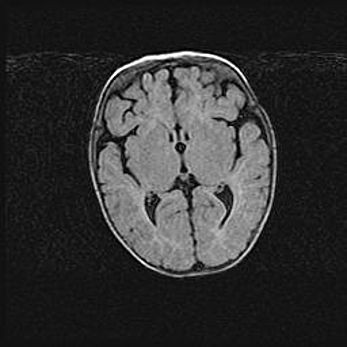

Лейкомаляция с кистозно-глиозной дегенерацией головного мозга.

Возраст: 2 месяца 25 дней

Вес: 6400 г

Окружность головы: 40 см

Срок гестации: 41 неделя

Лейкомаляцию относят к ишемически-гипоксическим повреждениям головного мозга, диагностируемым у новорожденных. При лейкомаляции в головном мозге обнаруживают очаги некроза, возникшие после тяжелой гипоксии и нарушения кровотока. В процессе морфогенеза очаги проходят три стадии: 1) развития некроза, 2) резорбции и 3) формирования глиозного рубца или кисты. Перивентрикулярная лейкомаляция (ПЛ) встречается примерно в 12% случаев среди новорожденных, обычно – у недоношенных детей, причем, частота ее зависит от массы, с которой младенец появился на свет. Наибольшее число малышей страдает лейкомаляцией, если масса при рождении 1500-2500 г.